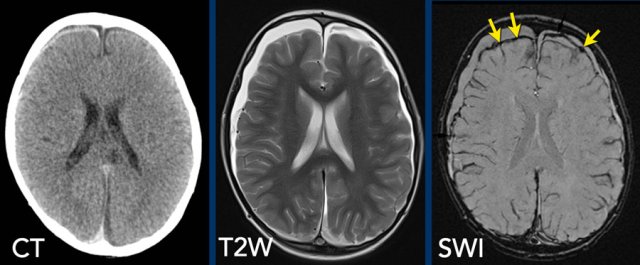

MR

examination is more sensitive in detecting subdural hematomas.

In all

cases we advise to add susceptibility weighted imaging (SWI) sequences to the

imaging protocol.

Images

Subtle subdural hematoma on CT is seen to a better advantage on

T2-weighted MRI and the hemosiderin deposits are evident on the SWI (arrows).